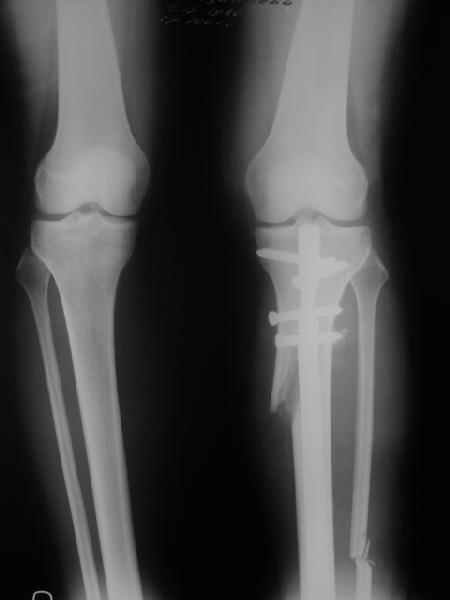

Снимки в приложении - фас сравнительный с неоперированной ногой. Жду критики.

It is very interesting to me that as you have derotated the tibia you have centred the patella, I think and the prox tibia looks much more anatomic.